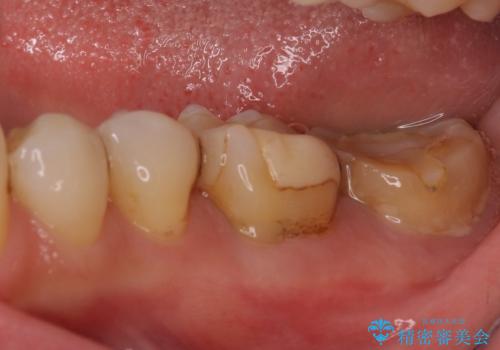

詰め物と歯に隙間ができており、既に根管治療をされた歯であったため、フルジルコニアクラウンにて補綴治療をすることとしました。

咬んだときに違和感があるとのことだったので、根管治療を事前におこなうこととしました。